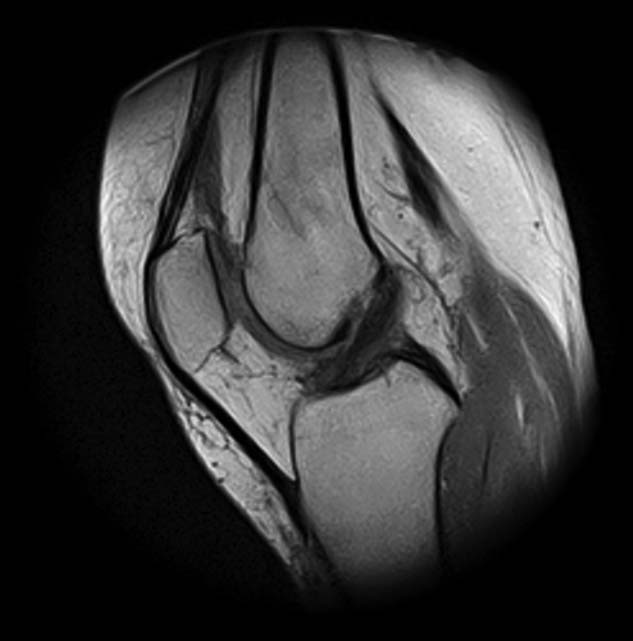

[Ortho] Показания для артроскопии

1. травма 5 лет назад - "ударилась коленом", с тех пор боли в суставе

3. стандартные рентгенограммы с небольшими изменениями - сужение

медиальной суставной щели

4. вес пациентки 80 кг, рост 165

5. сустав клинически стабилен